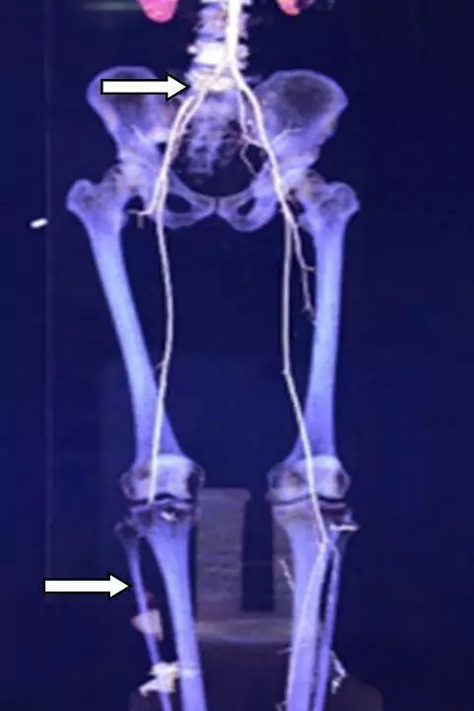

因各医保都处于年终结算期间,值班医生安乾积极帮助患者沟通医保转诊事宜,同时以最短的时间完成术前检查。血管外科崔文军副主任医师也在第一时间赶到医院,因同时两名患者需要急诊手术,又紧急通知夜班医生王颖主治医师赶到医院,协助完成第二名患者的信息采集和术前检查的完善。很快两名患者的病情都得以明确:来自濮阳的患者是外伤导致右侧股动脉损伤,当地医院无手术条件,仅予以简单缝合后予以止血钳钳夹(见图1),下肢皮温冰凉,末梢循环差,濒临坏死。来自驻马店的患者为急性下肢动脉栓塞,CTA提示腹主动脉下段及右侧髂总动脉血栓形成,血栓脱落后导致膝下动脉全部闭塞(见图2),右足皮温凉,皮色紫绀,趾端已出现坏死(见图3)。明确病情后,崔文军副主任医师及时向郑州大学五附院副院长、血管外科首席专家王兵教授汇报。王兵教授指示:手术指征明确,手术需争分夺秒!

图2 下肢动脉CTA